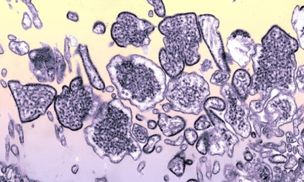

Nowa groźna choroba z Chin. Wirus Nipah zabija 75 proc. zarażonych